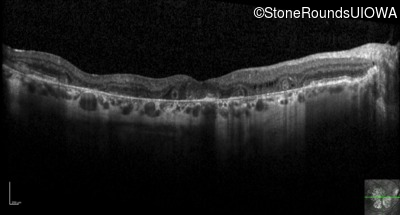

Optical Coherence Tomography - Right - 20/25

Exemplar / OCT Stack

OCT Stack

Optical Coherence Tomography - Left - 20/25 -2